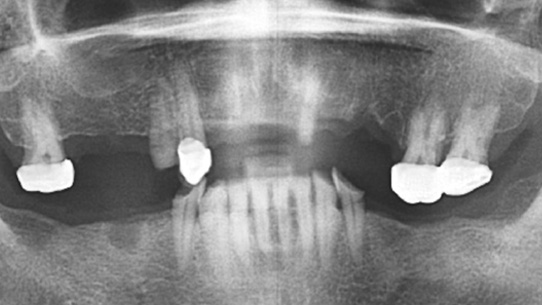

오래된 브릿지가 떨어지고 치아 결손이 심한 상태로 내원한 고혈압 환자분. 혈압이 정상 수치보다 높아 내과와 연계하여

혈압을 90~140 사이로 조절하여 총 13개의 임플란트를 식립 하였습니다.

고혈압의 경우 복용하시는 약이나 혈압, 혈당수치로 인하여 지혈이 어렵거나 면역력이 약해져 있어 수술 시 의료진의 노하우와

내과진료 연계가 가장 중요한 부분입니다.